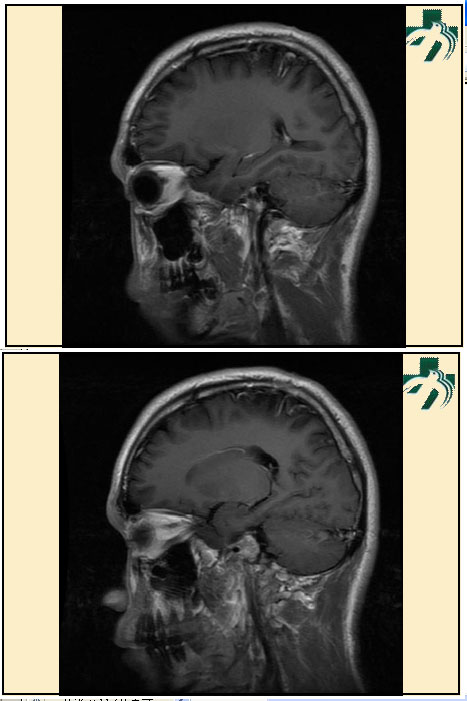

奴卡氏菌感染

第九期三博

读片会

病例之四

北京协和医院 提供

男性,22岁。自觉虫咬后皮疹、肢体麻木4月